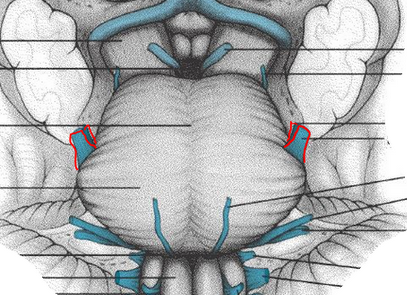

desribe the relationship to the absudcens and facial nuceli in the pons.

facial ncuelsu is more rostral and lateral but loops caudally around the abduscens forming the genu of the facial nerve (causes the bump or the facial colliculus)